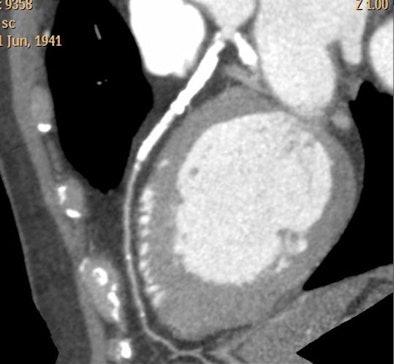

![]() |

| CTA interpretation is complicated by heavy coronary artery calcification; flow analysis could potentially aid diagnosis in such cases. All images courtesy of Dr. Henning Bovenschulte. |